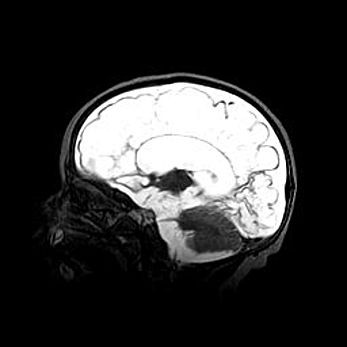

Множественные кисты обоих полушарий головного мозга, наибольшая из них в правой затылочной области. Ассиметричная атрофическая гидроцефалия.

Возраст: 7 месяцев

Вес: 5660 г

Пол: мужской

Окружность головы: 41,5 см

Срок гестации: 28-29 недель

Кисты головного мозга развиваются в результате многоочаговых некрозов вещества мозга и возникают вследствие перенесенной перинатальной инфекции, менингитов, энцефалитов, асфиксии, родовой травмы, расстройств мозгового кровообращения различного генеза. Образованию кист в веществе головного мозга плодов и новорожденных способствуют такие факторы, как высокое содержание в нем воды, недостаточная (или отсутствие) миелинизация и слабая астроглиальная реакция на повреждение.

Кисты могут сочетаться с гидроцефалией и другими поражениями головного мозга.